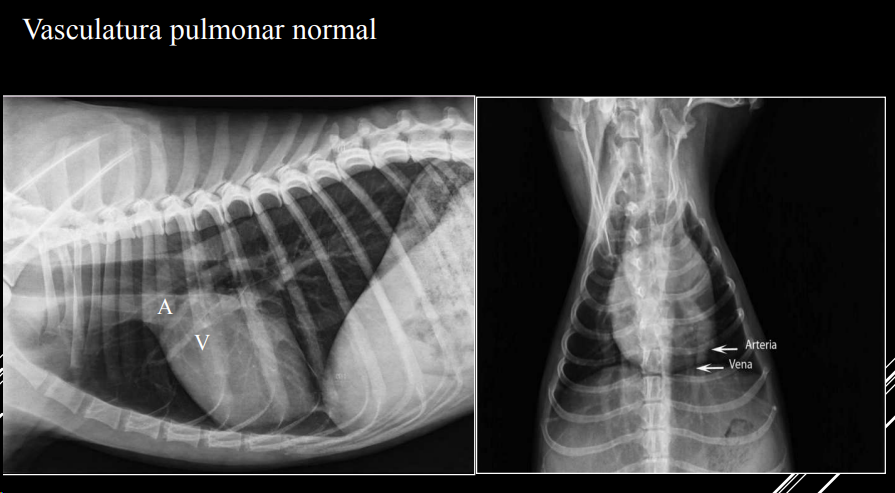

PATRÓN VASCULAR

- Cambios en tamaño, densidad o forma de vasos.

- Arteria y vena lobulares craneales del mismo tamaño.

- Comparación: grosor ≈ 4ª costilla (LL) o 9ª costilla (VD).

- Hipervascular o hipovascular.

- Posible mineralización (uremia, filariosis).

- Tortuosidad o cortes bruscos en arterias pulmonares → filariosis.